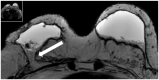

The surgical procedure of AFT and follow-up with imaging modalities including mammography (MG), ultrasound (US), and MRI in patients with a total breast reconstruction with AFT are summarized to illustrate the radiological normal and suspicious findings for malignancy.

Imaging after a total breast reconstruction with AFT appears to be based mostly on benign imaging findings with an overall low biopsy rate. As higher volumes are injected in this technique, the risk for the onset of fat necrosis increases. Imaging findings most often are related to fat necrosis after AFT. On MG, fat necrosis can mostly be seen as oil cysts. The occurrence of a breast seroma after total breast reconstruction with AFT is an unfavourable outcome and may require special treatment. Fat deposition in the pectoral muscle is a previously unknown, but benign entity. Although fat necrosis is a benign entity, it can mimic breast cancer (recurrence).